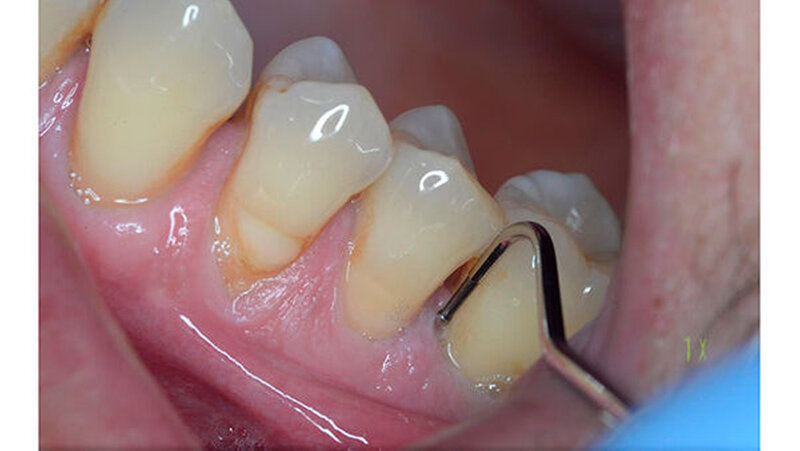

Ein 51-jähriger sportlich muskulöser Patient mit kariesfreiem Gebiss stellte sich zur konsiliarischen Untersuchung vor einer Operation der Kieferhöhle vor. Auf dem OPT imponieren der im Oberkiefer deutlich erkennbare horizontale Höhenverlust mit starker vertikaler Komponente in Regio 15/16 sowie der im Unterkiefer starke vertikale Knochenverlust in Regio 36. Allgemeinerkrankungen oder Medikationen wurden anamnestisch verneint.

Die CT-Aufnahmen zeigen eine deutliche bis zum Orbitaboden heranreichende Totalverschattung der rechten Kieferhöhle. In Höhe des Zahns 16 zeigen sich periradikuläre Rarefikationen als Hinweis auf eine aggressive lokale Parodontitis.